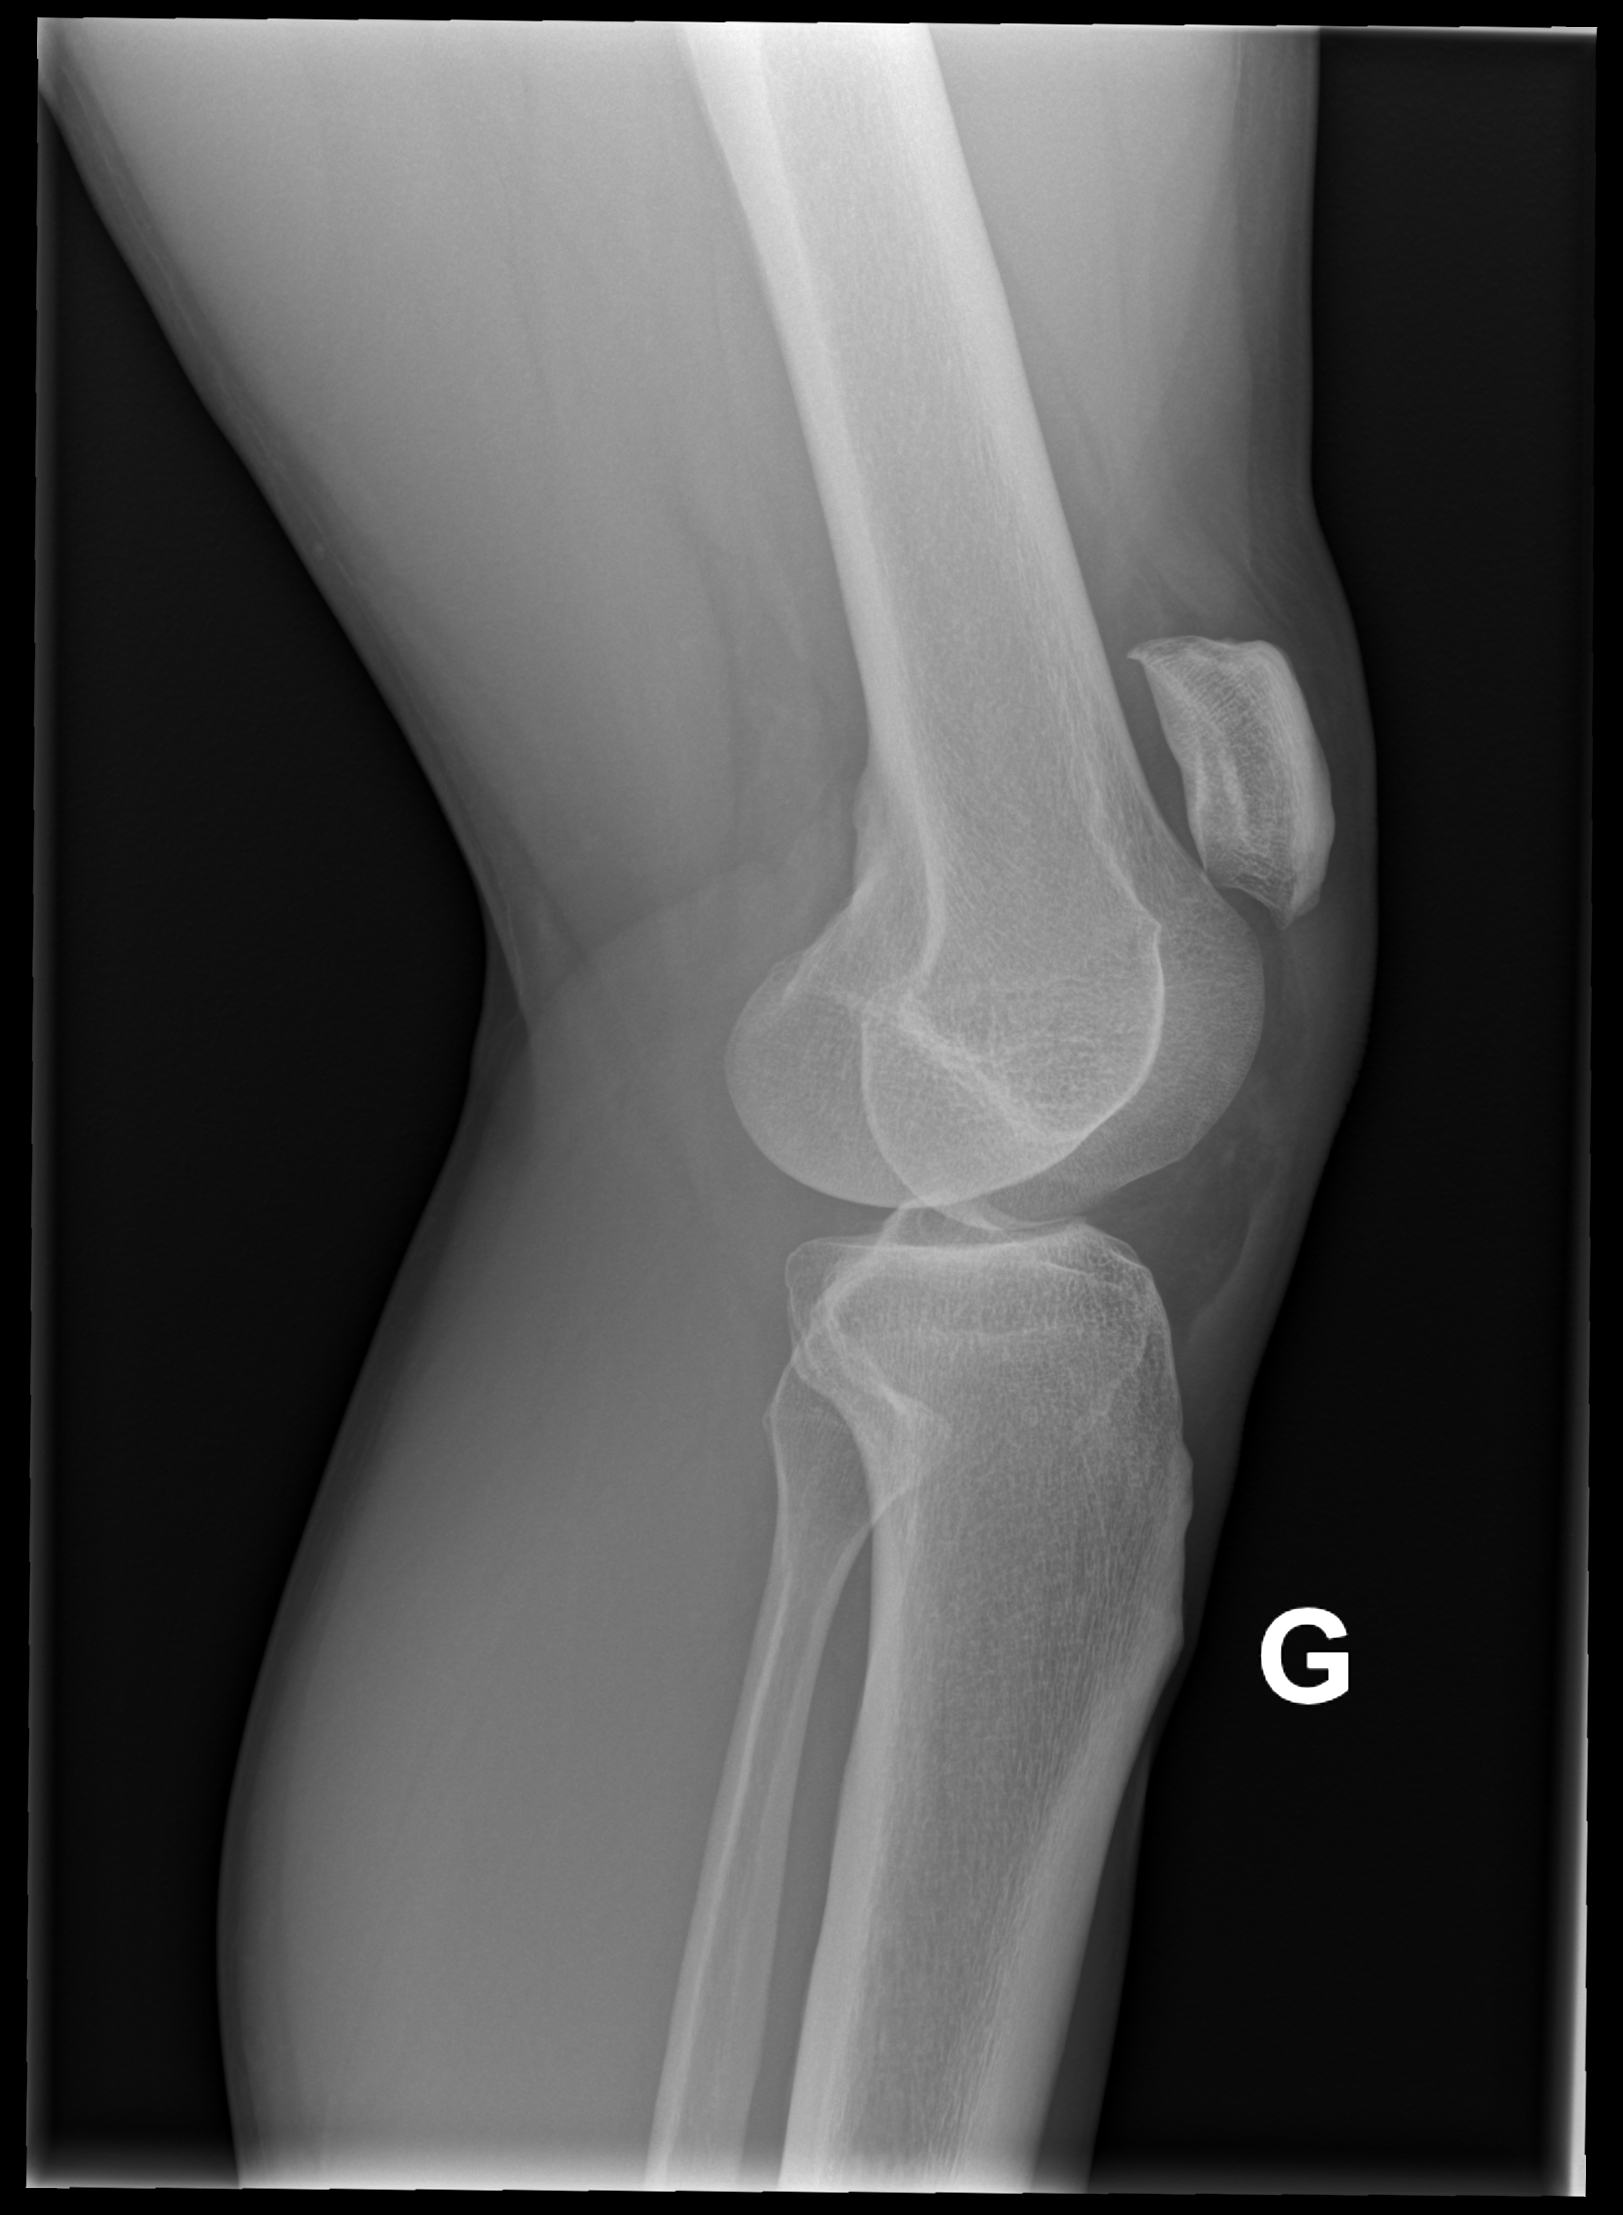

A l’examen clinique, le genou est légèrement tuméfié. La rotule semble ascensionnée et un creux est palpé sur le trajet du tendon rotulien. L’extension active est impossible. Sur les radiographies standards face et profil du genou, la rotule est ascensionnée.

Lorsque l’incidence axiale (ou défilé fémoro-patellaire, genou fléchi à 30°) est réalisée, l’image est décrite comme un « lever de soleil » avec une disparition de l’interligne articulaire et la superposition de la rotule avec les condyles fémoraux.